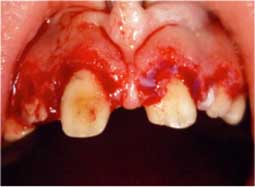

Extraction des dents temporaires, élongation coronaire chirurgicale des secteurs antérieurs supérieur et inférieur (Fig 5) et freinectomie (Fig 6).